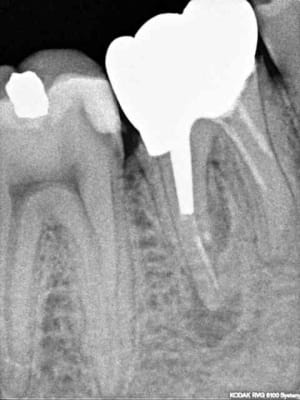

C_ramik_volution_y0hfwi.jpg